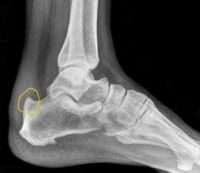

هي العملية الاولى من نوعها في العراق اجراها اخصائي جراحة العظام والكسور الدكتور نوار نعمة الفتلاوي في مدينة الصدر الطبية للمريضة (ص ح) ذات الـ٤٨ سنة من سكنة محافظة النجف الاشرف و التي راجعت المستشفى وهي تعاني من نتوء عظمي في عظم الكعب والتهاب الوتر الأخيلي مسبباً آلام لفترات طويلة لم تنجح معها كل طرق العلاج التحفظي و هذه الأعراض تبينت بعد اجراء الفحوصات الشعاعية للمريضة .